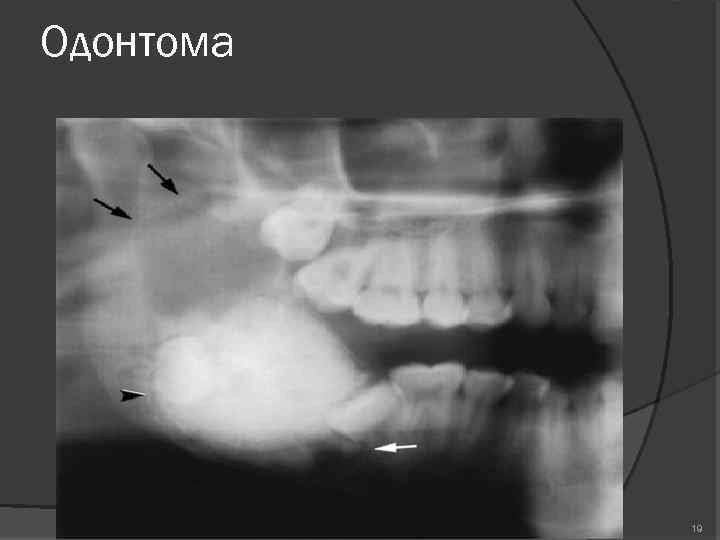

Одонтома нижней челюсти: фотографии и медицинская информация

Раздел: Фотобанк решений